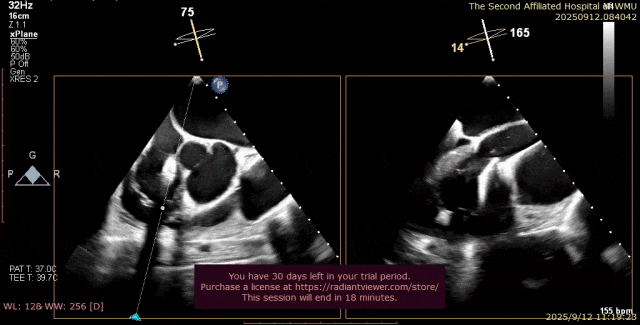

心脏超声示左室增大,二尖瓣2、3区脱垂伴重度反流(腱索断裂),Carpentier分型Ⅱ型,典型Barlow综合征表现;二尖瓣开放面积5.0cm²,3区瓣环内径31mm,前叶长22mm、后叶17mm,前叶收缩期关闭瓣体部分呈拱形突向左房腔,瓣膜游离缘对合欠佳,可见腱索断裂,长度9mm;2区瓣环内径32mm,前叶长22mm、后叶10mm,前后叶均可脱垂;三尖瓣重度反流。CDFI示瓣口重度偏心性反流,反流束沿主动脉后壁走行,肺静脉收缩期可见反向频谱。

术前超声

图片